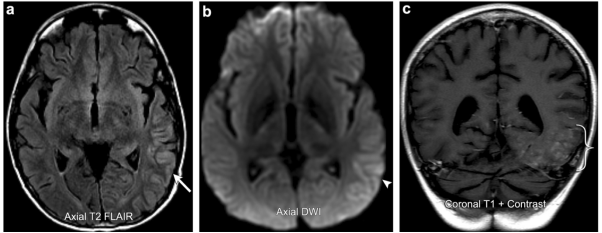

案例5: SMART综合征

31岁男性,10年前后颅窝非典型畸胎样横纹肌肿瘤切除术及放疗病史,现在出现持续性头痛,视野缺损,一天来出现找寻词语困难。磁共振图像显示脑回增厚和T2 FLAIR信号增高涉及到的左颞叶、顶叶和枕叶的大部分后方皮质(箭头所指)。伴有轻度弥散受限(箭头)和脑回增强(括号)。随访脑电图无癫痫活动和后续症状得到缓解。影像学表现及临床过程与SMART综合征相一致。